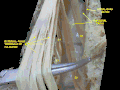

Spinal cord. Spinal membranes and nerve roots. Deep dissection. Posterior view.